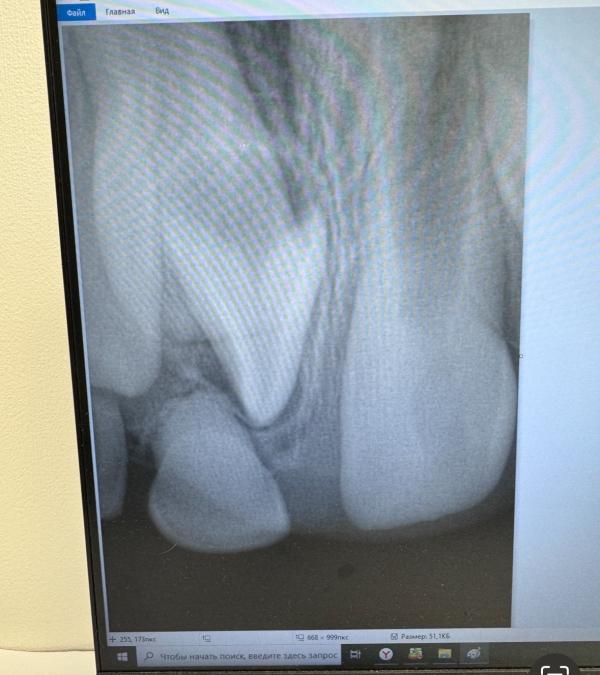

По снимку левый все таки вылезет, как думаете?

Он там один и без корня похоже, так себе на будущее 😄